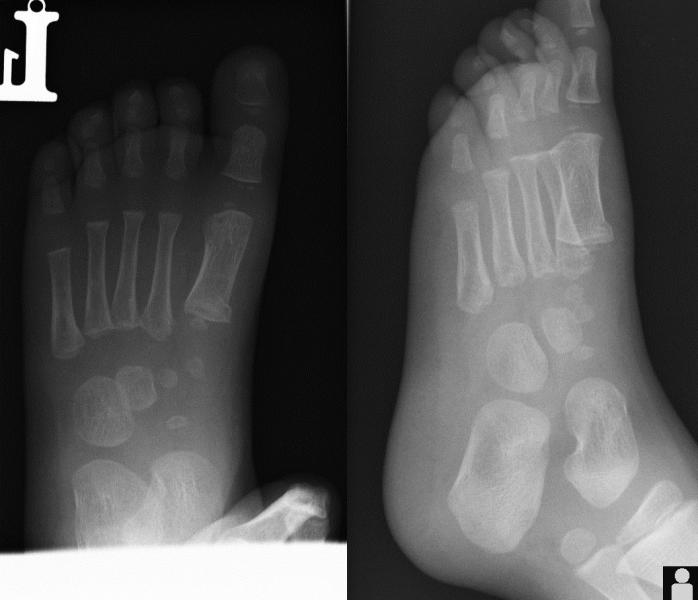

Przypadek 3: 2-letni chłopiec po urazie śródstopia lewego. Chód utykający, niewielki obrzek grzbietu stopy lewej.

Rozpoznanie: Złamanie podokostnowe przynasady bliższej I-ej kości śródstopia lewego.